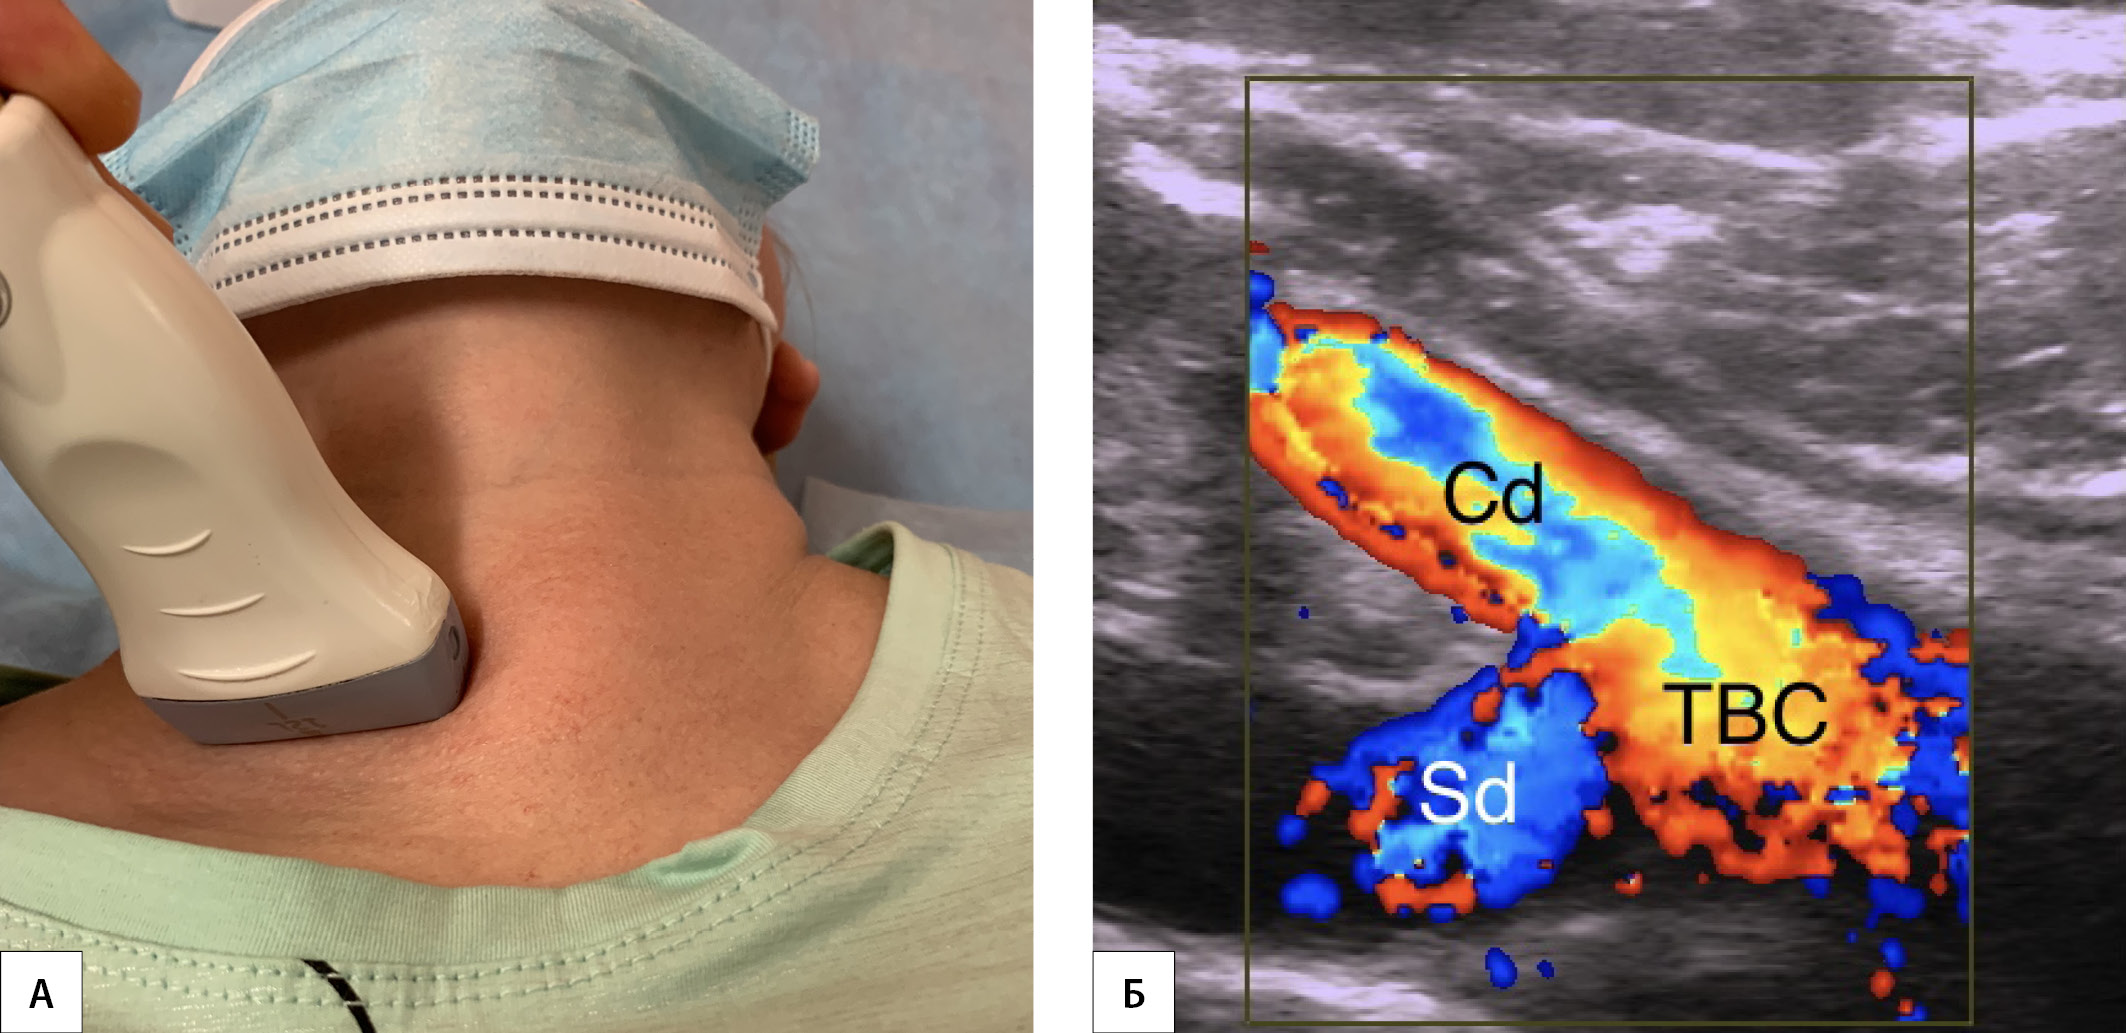

МАТЕРИАЛЫ И МЕТОДЫ. В исследование включены пациенты, которым выполнялись операции на щитовидной или околощитовидных железах с выделением правого нижнего гортанного нерва. В предоперационном периоде проводились УЗИ сосудов шеи с визуализацией брахиоцефального ствола (Y-признака) и правой аберрантной подключичной артерии (AL-признак). При интраоперационном выявлении невозвратного гортанного нерва в послеоперационном периоде проводилась компьютерная томография сосудов шеи.

РЕЗУЛЬТАТЫ. В исследование включены 1476 пациентов. Y-признак отмечен у 1338 (90,7%) пациентов. У данного контингента больных определялась типичная анатомия возвратного гортанного нерва. В 138 (9,3%) случаях Y-признак выявить не удалось. В этой подгруппе в 20 (1,4%) наблюдениях отмечены невозвратный гортанный нерв и правая аберрантная подключичная артерия. Таким образом, чувствительность Y-признака в диагностике нормальной анатомии возвратного гортанного нерва составила 100%, специфичность — 91,9%, положительная прогностическая ценность — 14,5%, отрицательная прогностическая ценность — 100%. Напротив, AL-признак отмечен у всех пациентов с невозвратным гортанным нервом и правой аберрантной подключичной артерией. Ложноположительных и ложноотрицательных результатов не отмечено. На основе анализа интраоперационных картин выделено три варианта невозвратного гортанного нерва: I тип (верхний) — расположен позади верхней трети доли щитовидной железы, имеет прямое нисходящее направление и образует угол к гортани в 30–50°; III тип (нижний) — имеет прямое восходящее направление (имитирует ход возвратного гортанного нерва) и образует угол к трахее в 30–50°; II тип (средний) — все варианты невозвратного гортанного нерва, расположенного между I и III типами.

ЗАКЛЮЧЕНИЕ. Выявление брахиоцефального ствола (Y-признака) при УЗИ подтверждает наличие у пациента возвратного гортанного нерва (чувствительность 100%), а визуализация правой аберрантной подключичной артерии (AL-признака) определяет наличие невозвратного гортанного нерва (чувствительность и специфичность 100%).

1. Рисунок 1. УЗИ брахиоцефального ствола. | |